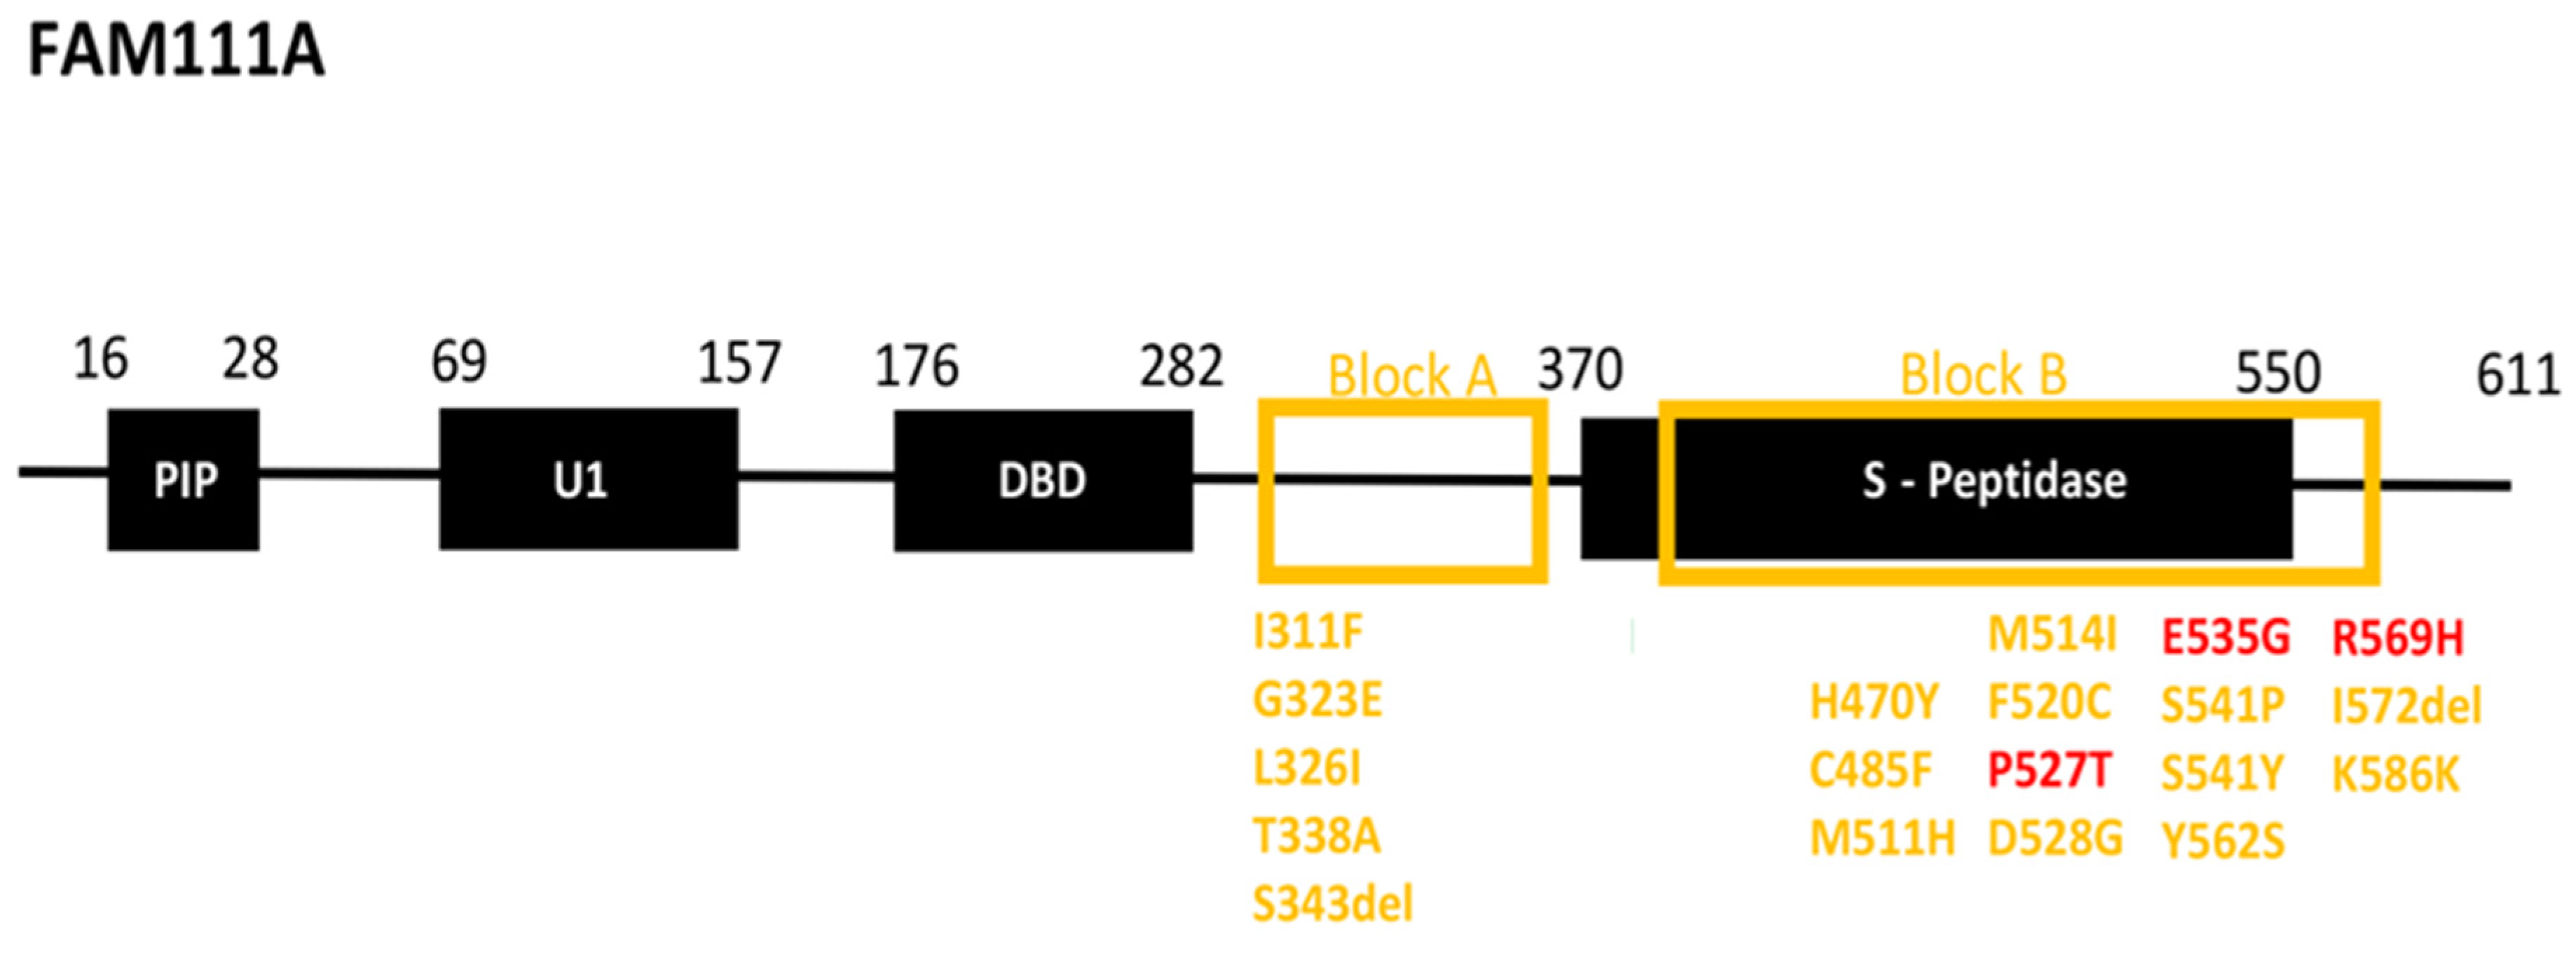

3.2. Patient Variant Analysis